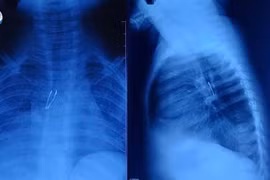

Hình ảnh kiểm tra vùng hố yên - trên yên cho thấy sau phẫu thuật u sọ hầu, hiện không còn khối khu trú. Kết quả chẩn đoán hình ảnh còn ghi nhận vài nốt thoái hóa chất trắng thùy trán phải (Fazekas 1), tổn thương cũ vùng thái dương phải, giãn nhẹ sừng thái dương não thất bên phải và viêm xoang chũm phải. Đặc biệt, kết quả xét nghiệm Natri máu tăng, cho thấy áp lực thẩm thấu máu tăng và áp lực thẩm thấu niệu giảm.

Từ các triệu chứng lâm sàng và kết quả chẩn đoán, các bác sĩ đưa ra kết luận, bệnh nhân mắc suy tuyến yên sau phẫu thuật u sọ hầu - rối loạn nội tiết hiếm gặp.

Cảnh báo biến chứng suy tuyến yên sau phẫu thuật u sọ hầu. (Ảnh: Minh họa/Nguồn GD&TĐ).